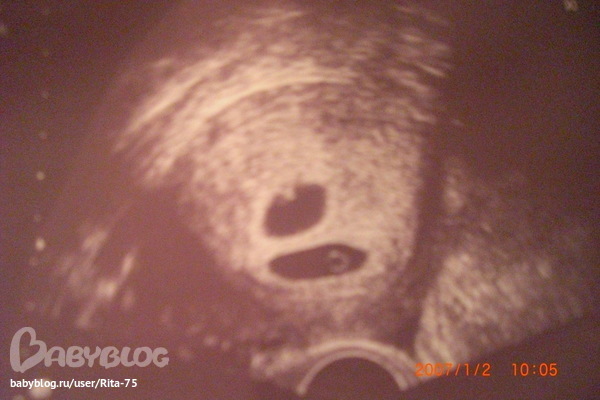

Ритта

Я при задержке в 5 дней уже лежала на кресле у гинеколога и пялилась в экран УЗИ,одно тёмное пятнышко,доктор сказал,что это точно ваша беременность,я была уже рада и всё-таки спросила,а что ЭТО такое,показывая на второе тёмное пятнышко менее заметное,на что доктор ответил:"Я вот тоже думаю,но у меня есть все основания пологать,что это ваша ВТОРАЯ беременность",придёте через неделю -скажу точно,пока что я ничего внутри второго яйца не вижу,срок маленький и сказал,что это может быть пустое яйцо,которое рассосётся само собой.Всю неделю я не могла спать,есть и всё думала,мы с мужем в шоке были всю неделю,но когда я снова поехала к врачу-мы с мужем уже любили обоих и я на УЗИ чётко увидела две оплодотворённые яйцеклетки,была рада,от шока было время отойти и уже радовалась и гордилась собой,мне сейчас хочется кричать:"Посмотрите на меня,я беременная двойней! Это так интересно,до сих пор не верится,что во мне двое. Но первое впечатление-это шок,я ни про кроватку не думала,ни про коляски,а думала я про то,как с ними двумя быть? Я привыкла ростить по одному,а тут двое и с каждым надо поиграть,поговорить,ладушки,песенки и прочее....всё вдвойне.